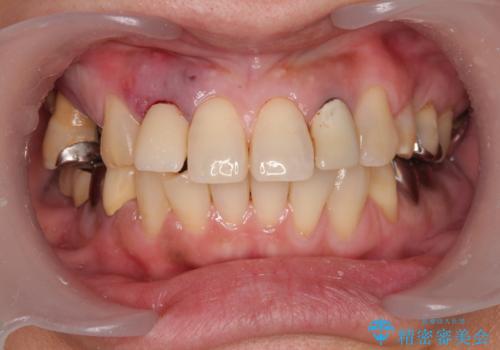

抜歯即時埋入インプラントによる補綴治療の特徴は、短期間であることや処置数が少ないことが挙げられます。また、表側の歯肉の陥凹を避けることができるというメリットがあります。しかしながら、今回は歯根破折の程度が酷く、やや膨らみを失うこととなりましたが、スムーズに治療を終えることができました。

臼歯部は前歯以上に炎症が酷く、抜歯即時埋入不可と判断されましたが、従来法よりは短期間で終えることができました。